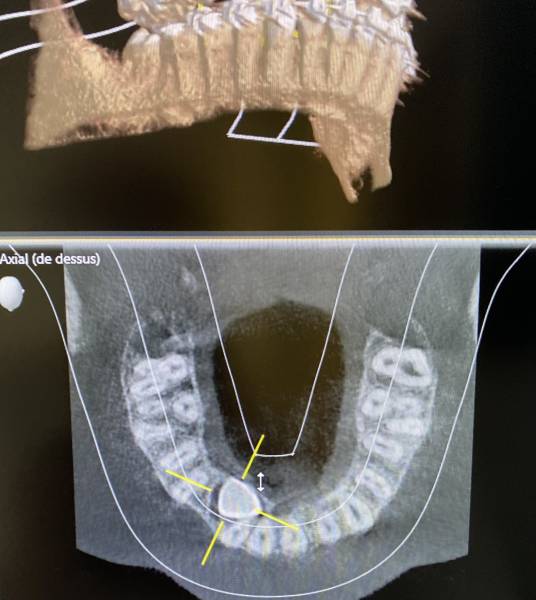

L'utilisation de l'imagerie 3D est quant à elle indiquée pour visualiser les bases osseuses pour la planification de chirurgie implantaire, de greffe osseuse, la détection des limites périphériques d'un kyste, la localisation de dents incluses (canine incluse au palais ou dent de sagesse), la visualisation de l'anatomie canalaire pour les traitements endodontiques (dévitalisation).